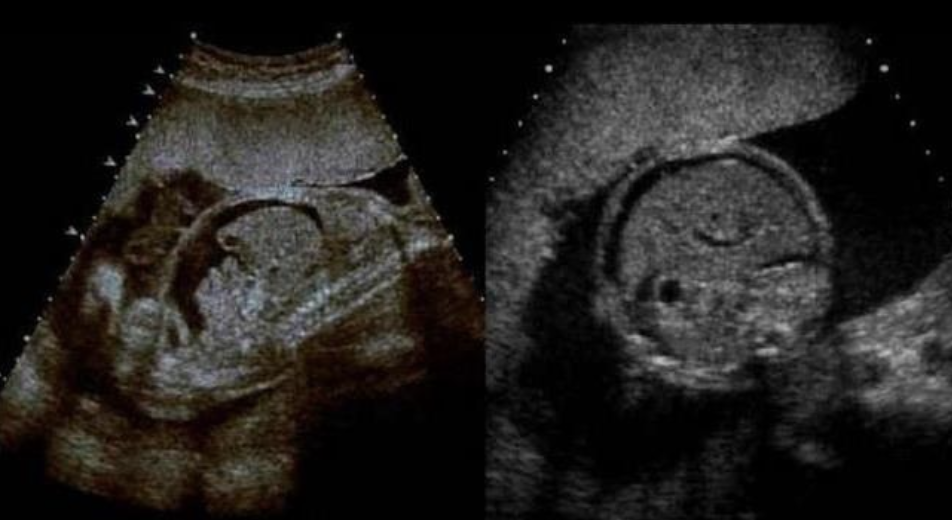

![<p>a) twin reversed arterial perfusion sequence [<strong>TRAP</strong>]</p><p>b) twin anemia polycythemia sequence (<strong>TAP</strong>)</p><p>c) a triploidy fetus + normal fetus</p><p>d) vanishing twin syndrome</p>](https://knowt-user-attachments.s3.amazonaws.com/93193faf-e189-4587-9739-07cd68e6222a.png)

a) twin reversed arterial perfusion sequence [TRAP]

b) twin anemia polycythemia sequence (TAP)

c) a triploidy fetus + normal fetus

d) vanishing twin syndrome

a) twin reversed arterial perfusion sequence